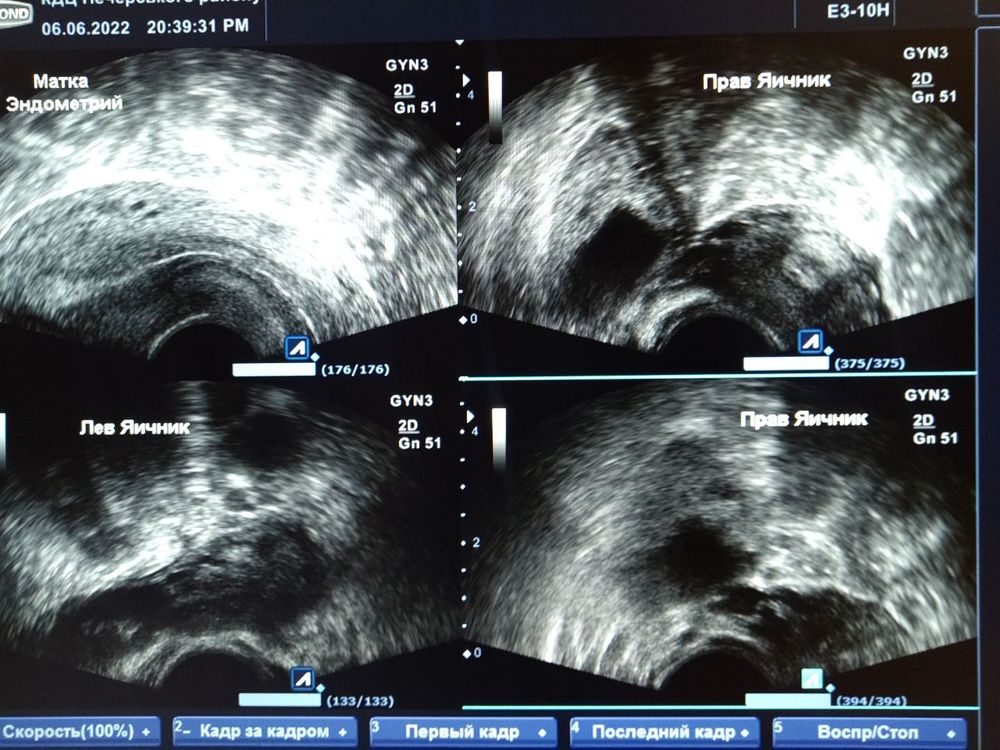

После низкого ХГЧ, мы пообщавшись со свои врачом решили не ждать пока ПЯ выйдет само, я приняла решение идти на медикаментозный аборт. Во-первых скажу что благодарна своему врачу,она дала подробную инструкцию вплоть до того что я на созвоне и в мессенджере постоянно контактировала, она предлагала если хочу лечь в стационар,но я решила что все будет дома.Во-первых хочу сказать что все прошло хорошо,я не думала что так подейсвтует быстро, боли были конечно адские вначале,выпила кетанов. Через неделю пришла на контрольное УЗИ.Меня еще мазало и врач сказала будет мазать немного,прописала свечи вибуркол,вместо ношпы,у меня от нее очень кружиться голова,а так все хорошо. Сказала у тебя все вышло,осталось немного эндометрия, но он еще выходит,больше пей воды и ставь свечи.Сказала у тебя идеальная гинекологическая картина,хоть фоткай да показывай в институтах как должно быть у здоровой женщины,сказала ты с какой картиной ко мне должна была прийти перед планированием)))А так же моя киста в правом яичнике размером 8 см почти полностью ушла, в левом тоже нет кисты.Посмотрела яичники, сказала вижу много созревших фоликулов,сейчас очень аккуратно,ты скоро очень станешь плодной,ты можешь сразу забеременнеть,но нужно восстановление организма 4-8 недель,так что пока запрет на половую жизнь, сказала прийти к ней еще через неделю.Вообщем пока я жду и востанавливаюсь,еще нужно проверить гормоны,потому что очень резко набрала вес, но честно даже раза что так вышло,все приходит вовремя.